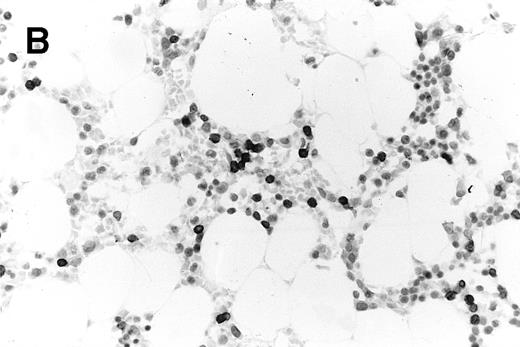

Trephine biopsy sections. (A) A patient with follicular centroblastic centrocytic lymphoma stained with hematoxylin and eosin showing low-volume, nodular disease (original magnification ×100). (B) A patient with T-lymphoblastic lymphoma stained with anti-CD3; cells with dark cytoplasm are CD3+ (original magnification ×400). These photomicrographs show the low level of lymphoma infiltration which in both cases was detected by PET.